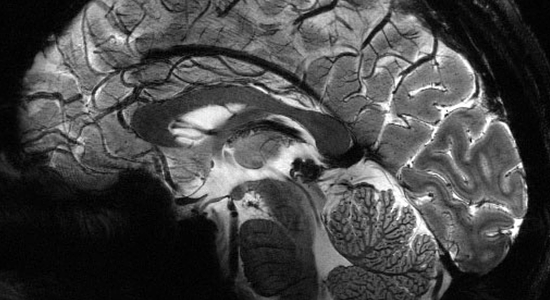

Les neurosciences, avec les techniques de neuro-imagerie apporte une meilleure connaissance de ces anomalies des relations cerveau-intestin et permettent d’envisager de nouvelles thérapeutiques médicamenteuses ou comportementales et cognitives pour soigner ces maladies de l’intestin.